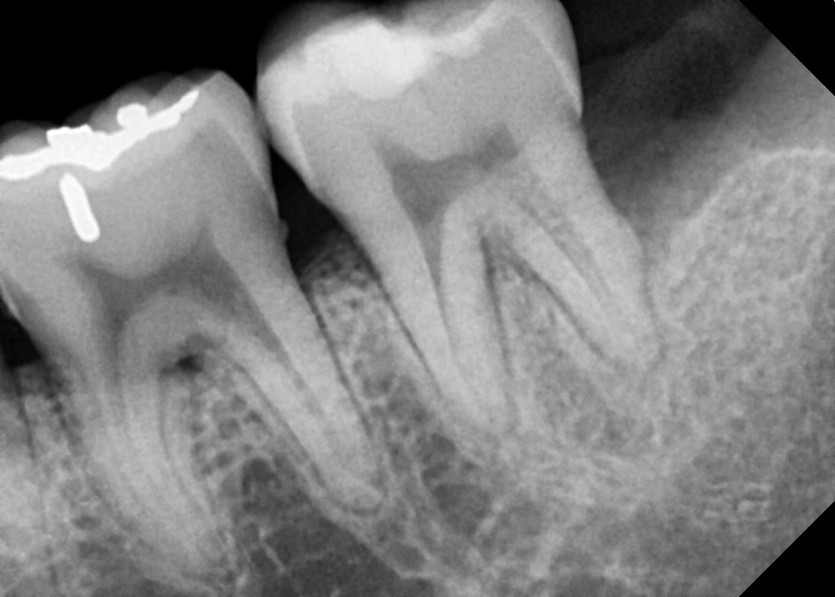

#38 사랑니 발치

구강 외과 전문의가 당일 발치했습니다.